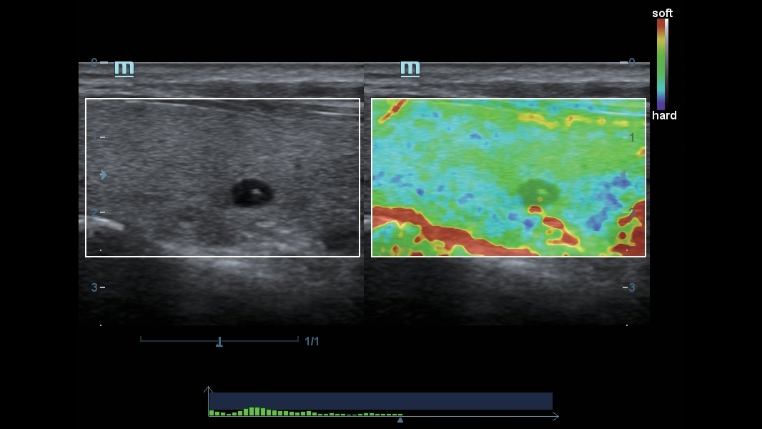

Tecnologie di imaging classiche: migliorare la qualitĂ a scopo diagnostico

Con l'applicazione delle tecnologie di imaging tradizionali, migrate da sistemi a ultrasuoni consolidati, DC-40 con Full HD offre immagini di qualitĂ estremamente dettagliate.

- iClear (tecnologia di imaging con riduzione del rumore)

- PSH(Phase Shift Harmonic Imaging)

- iBeam: ?tecnologia di imaging spaziale âCompoundâ